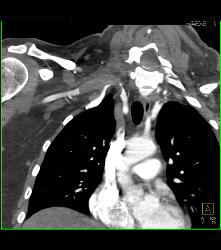

Cervical Rib With Occlusion of the Right Subclavian Artery- See Full Sequence